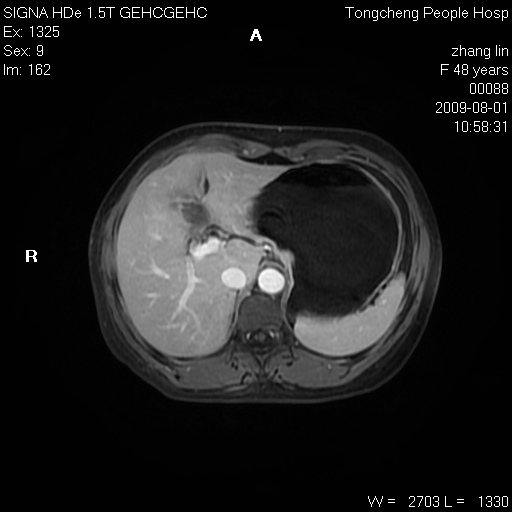

女,48岁。健康体检,彩超发现右肾占位性病变。平素健康。

临床诊断:右肾占位性病变,性质待定(囊肿?肿瘤?)。

上中腹部mr平扫+增强扫描,图像如下:

右肾上极见一类圆形病灶,t1wi呈等信号t2wi呈等高混杂信号,三期增强无强化,边界清---考虑囊肿出血。

同反相位均表现为等信号,病变无强化,考虑含蛋白的囊肿可能,弥散加权相或许有些帮助,